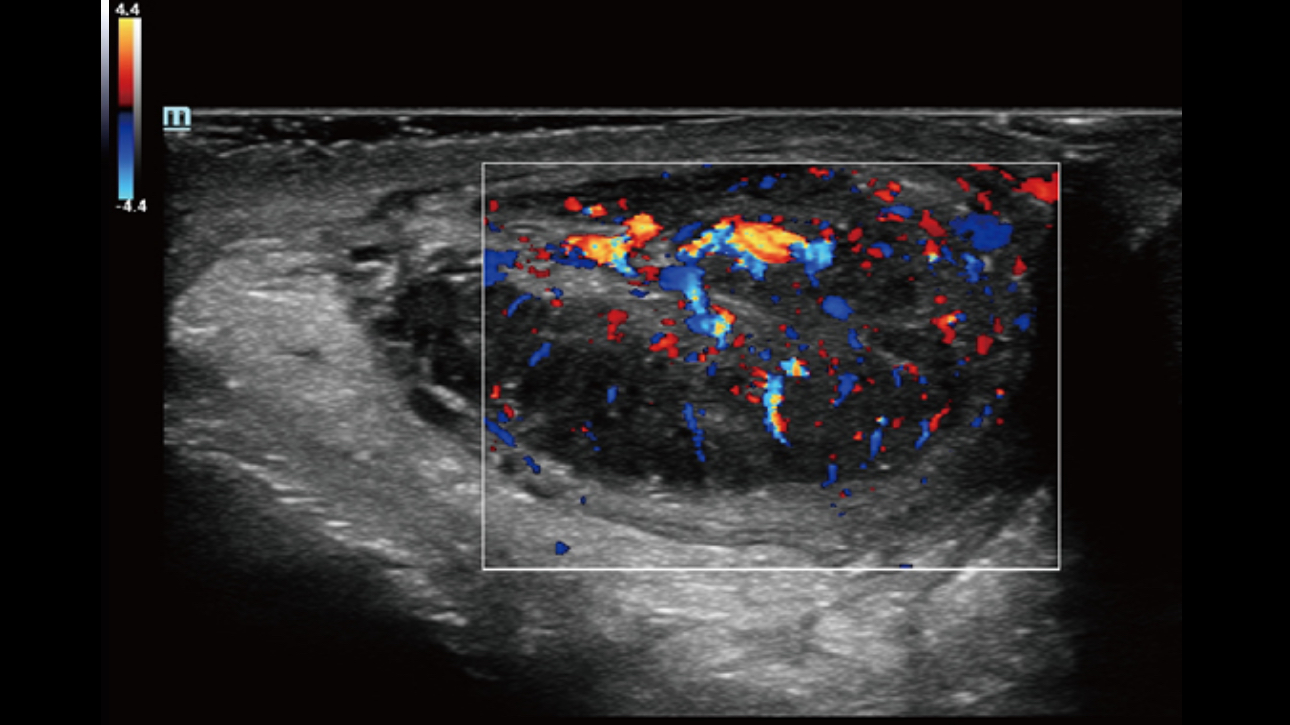

Dynamic Pixel Focusing technology allows the Resona 6 to achieve extreme uniformity in pixel level throughout the whole field of view. Now there's no need to adjust the focal positions to achieve uniformity across patient exams.

Channel data based ZST+ provides Enhanced Channel Data Processing for greatly improved imaging clarity. By multiple and retrospective channel data processing, it makes the best use of acoustic information for image improvement.

HD Scope: By processing channel data retrospectively, HD Scope enables tissue-specific enhancement with improved detailed information and image contrast on specific region of interest.